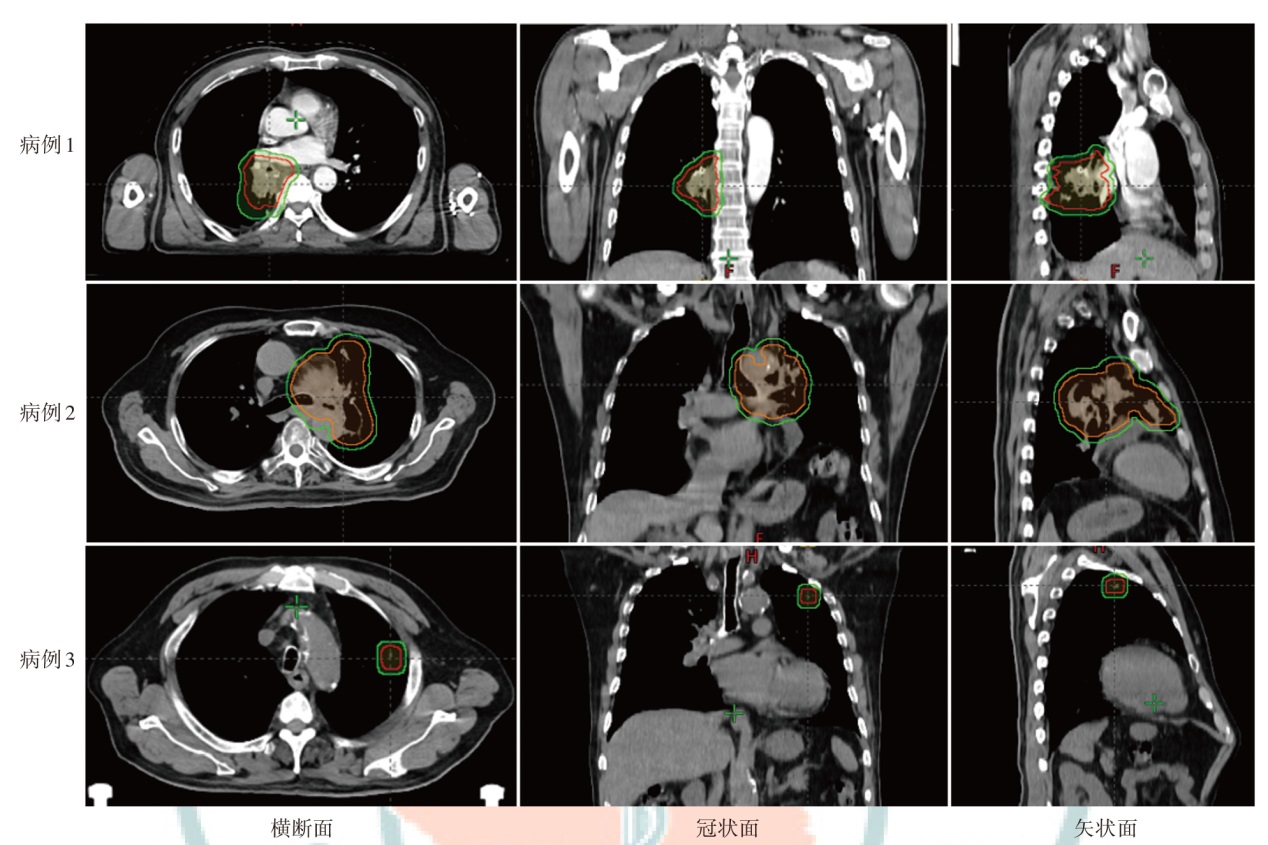

Objective To investigate the dosimetric characteristics of intensity modulated proton therapy (IMPT) and intensity modulated radiation therapy (IMRT) for lung cancers. Methods Three lung cancer patients (central-lower, central, and peripheral types) admitted to Shandong Cancer Hospital and Institute from January 2024 to May 2024 were selected as the research subjects. IMPT and IMRT plans were designed for each case based on the anatomical location of the clinical target volume and the dose constraints for organs at risk (OARs). Dosimetric parameters, including conformity index (CI), homogeneity index (HI), and gradient index (GI) for target coverage, as well as OARs dosimetric parameters were evaluated. The volume of additional dose deposition in the body was compared by assessing regions receiving 10%, 30%, and 50% of the prescription dose. Results For all three cases, IMRT plans demonstrated higher CI values (0.80, 0.60, and 0.79) compared to IMPT plans (0.61, 0.57, and 0.34). IMPT plans yielded lower HI values (0.07, 0.06, and 0.06) than IMRT plans (0.09, 0.15, and 0.09) and lower GI values (2.84, 2.47, and 4.56 vs. 4.91, 3.09, and 4.99 for IMRT plans). Compared with the IMRT plans, the low-dose region in the ipsilateral lung was significantly reduced in IMPT plans (V5 of the IMPT plans were 20.59%, 46.29%, 10.94%, respectively; V5 of the IMRT plans were 48.91%, 60.63%, 19.92%, respectively), but there was no significant advantage in the high-dose region compared to IMRT plans (V20 of the IMPT plans were 12.88%, 34.75%, 5.21%, respectively;V20 of the IMRT plans were 21.70%, 36.50%, 5.31%, respectively). The dose to the contralateral lung and heart was significantly reduced in IMPT plans [the Dmean of the contralateral lung in the IMPT plans were 0.08, 0.04, and 0.00 Gy (RBE), respectively, and those in the IMRT plans were 3.25, 1.18, and 0.55 Gy, respectively; the heart Dmean in the IMPT plans were 6.23, 7.04, and 0.00 Gy (RBE), respectively, while those of the IMRT plans were 18.33, 10.27, and 0.08 Gy, respectively). IMPT plans significantly reduced the volumes receiving 10% of the prescription dose by 65.94%, 25.57% and 72.47%, respectively, compared to IMRT plans. The volumes IMPT plans occupied by 30% of the prescription dose area in the body were reduced by 54.97%, 26.47% and 39.04%, respectively, compared to the IMRT plans. The volumes IMPT plans occupied by 50% of the prescription dose area in the body were reduced by 54.49%, 30.43% and 28.89%, respectively, compared to the IMRT plans. Conclusions IMPT plan significantly reduces the V5 of the ipsilateral lung, the Dmean of the contralateral lung and the heart, while maintaining target coverage compared with IMRT plan for lung cancers. However, IMPT plan does not show much more advantage than IMRT plan in the ipsilateral lung V20. IMPT can reduce the additional exposure volume within the body.